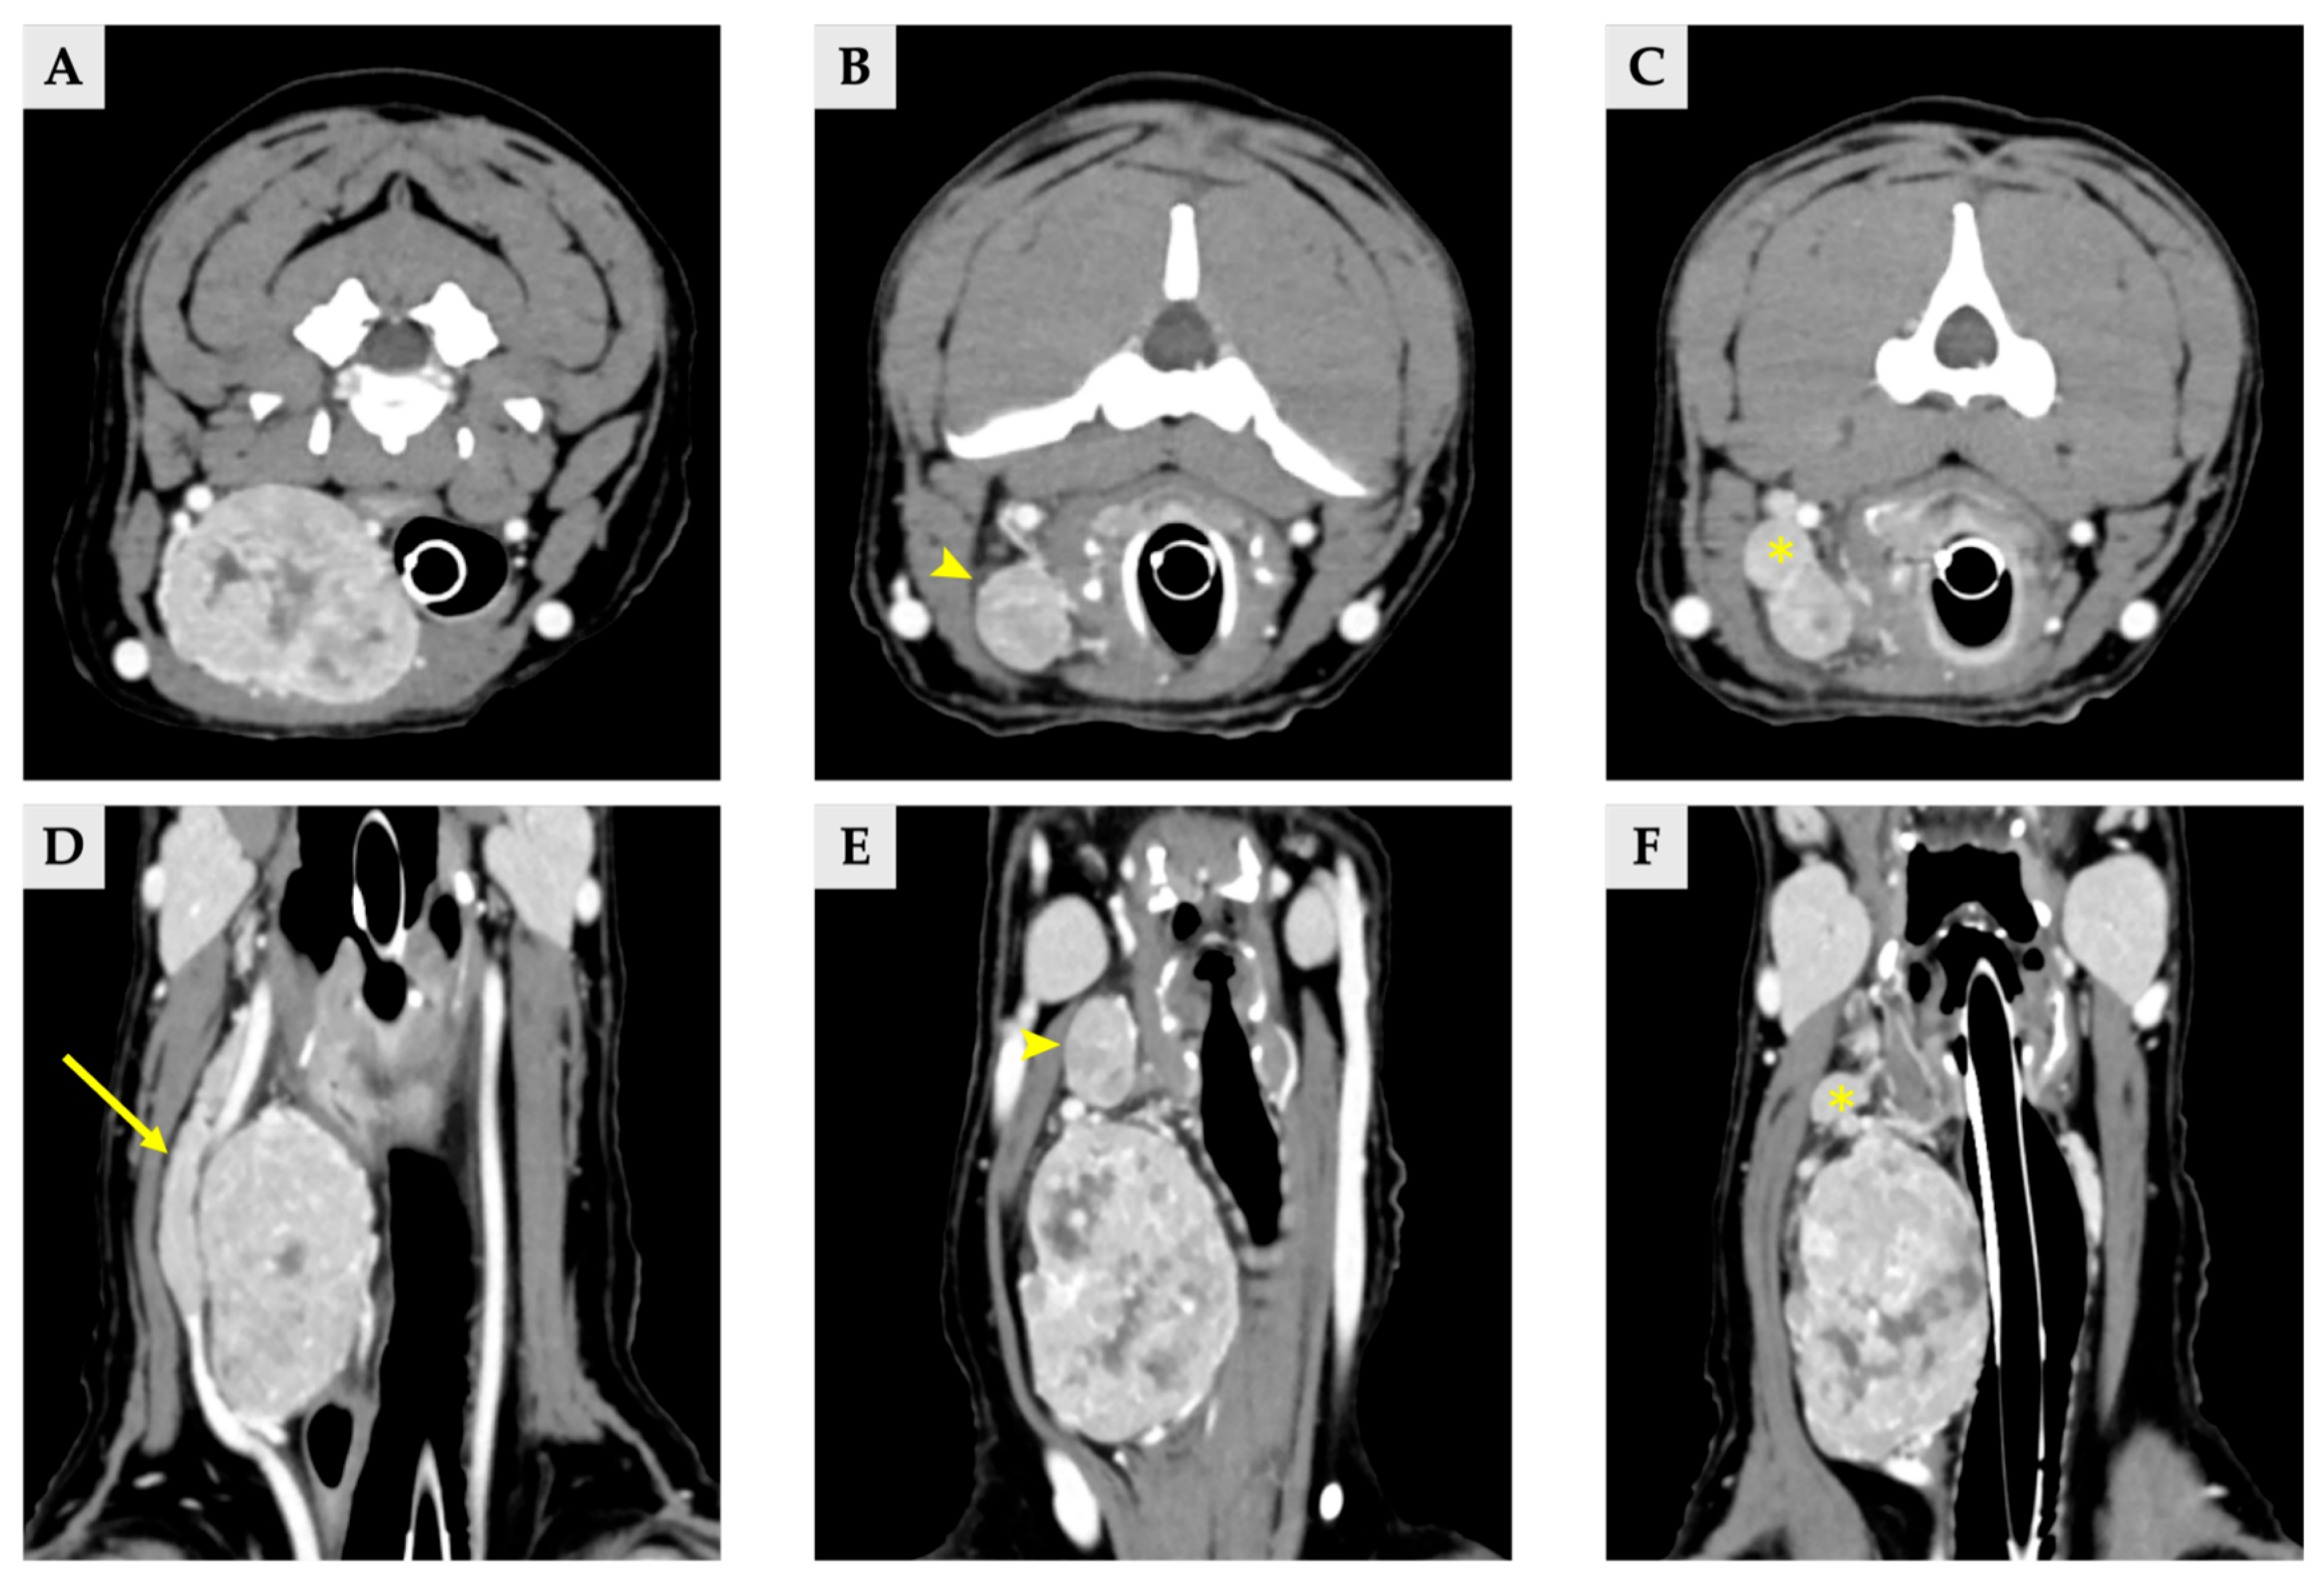

Radiographs demonstrated a soft-tissue opacity over the trachea at the level of C2–C5, causing leftward tracheal deviation (Figure 1). No pulmonary lesions were evident. CT confirmed three well-defined, separate right-sided cervical masses, including the largest palpable cervical mass, extending from the C1 to C5 levels (Figure 2). All three masses were clearly distinct from one another, with no visible continuity on cross-sectional imaging. Mass 1 measured 66.6 mm × 42.0 mm × 37.6 mm (approximately 56 cm3 in volume [14]) and originated from the right thyroid gland. It showed heterogeneous contrast enhancement and produced a filling defect within the adjacent right internal jugular vein, consistent with vascular invasion. Mass 2 measured 25.1 mm × 14.2 mm × 16.5 mm in size, located cranially to mass 1 without any structural connection, and the volume was 3.1 cm3 [14]. Mass 3 measured 11.5 mm × 11.5 mm × 8.6 mm in size, 0.7 cm3 in volume [14] and was positioned between mass 1 and mass2, lying dorsally to mass 2, and was likewise distinctly separated from the other lesions, and the total volume of three masses was approximately 60 cm3 [14]. The left thyroid gland appeared normal, whereas no normal thyroid tissue was identified on the right side at the corresponding anatomical level; instead, only the three masses were present. This finding supports the interpretation that these three lesions originated from the right thyroid gland.

Figure 2.

Delayed phase of CT scan image of three thyroid masses (A–C) transverse view, (D–F) dorsal view. (A,D) Images of right thyroid mass 1, demonstrating a filling effect of right internal jugular vein (arrow). (B,E) Right thyroid mass 2 (arrowhead). (C,F) Right thyroid mass 3, locating between the mass 1 and 2 (asterisk).